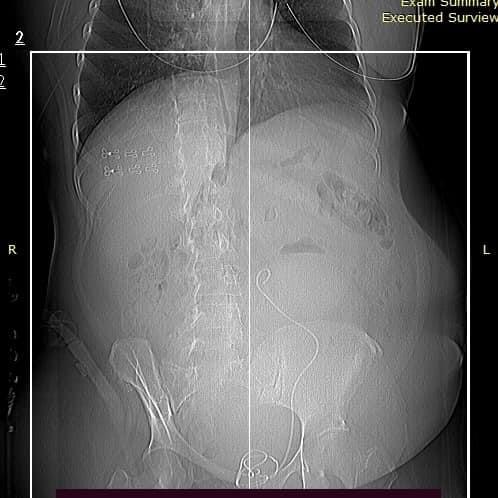

Про пухлину матки 51-річна львів’янка Руслана Кашемірова дізналася у 2018 році. Причиною звернення до лікаря стали постійні кровотечі та біль у животі. На УЗД медики виявили у жінки фіброміому – доброякісну пухлину матки – завдовжки 13 см. Новоутвір вже тоді розрісся в кишківник та артерії, однак пацієнтка боялася операції.

«Аби уповільнити подальший ріст фіброміоми та зупинити менструальний цикл – через кровотечі, Руслані призначили гормональний препарат. Згодом жінка набрала зайву вагу, але водночас в неї знизився апетит і з’явилося постійне відчуття наповненості шлунка. Фіброміома росла далі. Цьогоріч на черговому контрольному УЗД медики констатували: пухлина заповнила вже всю черевну порожнину пацієнтки. Іншого шляху, крім видалення, – не існує. Однак, Руслана знову відклала операцію – до осені», – зазначили у лікарні.

«Наші спеціалісти виявили причину лихоманки. Пухлина тиснула на нирки та сечовід, виникло запалення та реальна загроза життю. Тягнути вже не було куди. Потрібно було негайно оперувати. Спеціалісти гінекологічного відділення виконали тотальну абдомінальну гістеректомію, тобто видалили матку разом із пухлиною. Через розріз у черевній порожнині вони витягли велетенську фіброміому – вагою понад 5 кг. Хірургічне втручання минуло успішно.